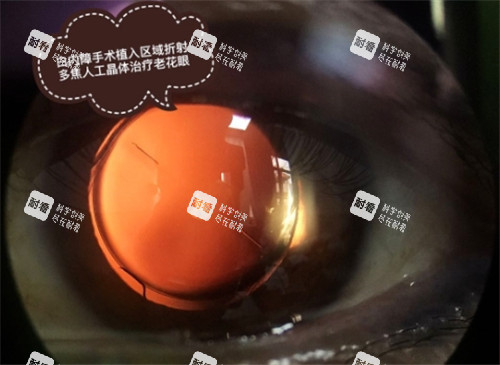

临床主流的超声乳化白内障吸除术,通过超声能量将混浊晶状体击碎并吸除,再植入人工晶状体,全程需要10-40分钟,术后眼部反应轻微,是日间手术的核心适配术式。

飞秒激光辅助白内障手术则通过激光完成切口、撕囊等关键步骤,精又准度更高、创伤更小,术后改善更快速,同样无需住院过夜,需要术后留观数小时。